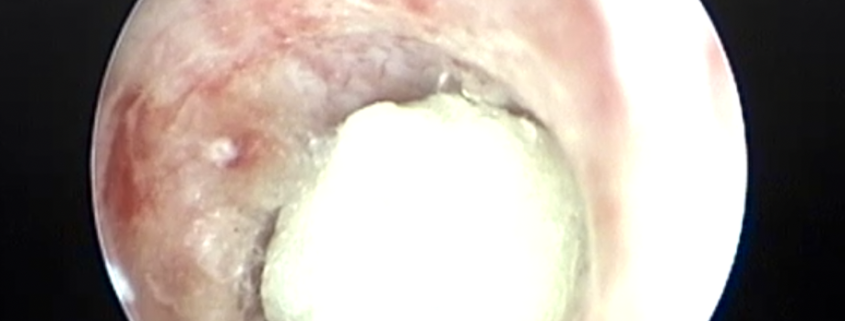

Cistoscopia litiasis uretral